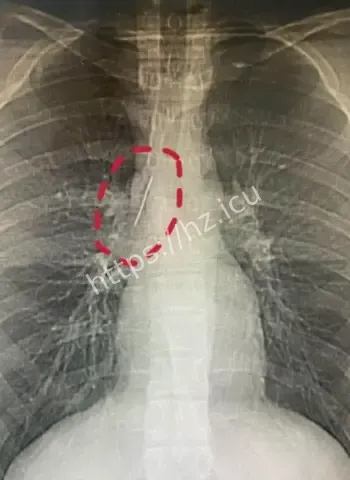

安徽17岁小伙-胸腔藏5厘米缝衣针-或1岁扎入17年无恙-参军体检发现

哎呦喂这事儿听起来就跟天方夜谭一样,一个安徽的17岁小伙子平时活蹦乱跳的,准备去参军体检,结果医生一照X光片子,眼睛直接瞪圆了,胸腔里居然稳稳当当藏着一根5厘米长的缝衣针。这针估计从小时候就钻进去了,整整17年啊,小伙子吃饭睡觉打球跑步啥都没耽误,身体愣是没闹过一点别扭。换成别人早疼得满地打滚了,他倒好,像没事人似的,这运气简直逆天到让人羡慕嫉妒恨。 想想这17年里,针就这么安静待着,没移位没发炎没刺着要害,估计是身体自动给它裹了一层保护膜,把它当成了自家摆设。

最离谱的是,这针很可能他1岁那会儿不小心扎进去的。小宝宝那时候到处乱爬乱抓,说不定妈妈正缝衣服,他一扑腾就中招了,结果针就这么悄无声息地进了胸腔。17年过去,他从奶娃娃长成大小伙,针却一直老老实实待着,没引起任何不舒服。平时感冒发烧都没多想过胸口,这适应力也太强了吧。 从道理上讲,小孩子身体正长着,组织慢慢把针包得严严实实,像给它建了个小房子隔离起来。没碰着肺叶心脏血管,纯靠运气加体质,简直是活生生的人体奇迹。

参军体检本来是查身体合不合格,谁知道成了挖宝现场。X光一扫,医生估计当时就傻眼了,这么大一根针亮闪闪地躺在胸腔里,小伙子自己都蒙圈了,心想我这身体里藏了啥秘密武器啊。幸好发现及时,要不然以后训练强度一大,万一针跑偏了,后果真不敢想。 这事儿也给大伙提了个醒,重要关口体检千万别马虎,尤其是参军这种人生大事,啥隐藏问题都能揪出来。小伙子估计现在又惊又喜,喜的是没出大事,惊的是自己居然带了17年“隐形伴侣”。

深入扒一扒,这针为啥能跟身体和平共处这么久呢。首先位置挑得好,没扎着要害器官,胸腔空间大给它留了余地。其次人体有自我保护本能,会分泌纤维组织慢慢把它包裹住,防止感染和移位。小时候扎入,身体还在发育,适应起来更容易。再次可能没带细菌进去,运气成分占大头。 这案例搁医学上都算罕见,值得研究研究,说不定以后处理类似异物就有新办法了。不过小伙子以后肯定得做个小手术取出来,不然总是个小隐患。希望手术顺顺利利,他的参军梦还能接着追,这段经历以后说出去绝对是别人听不够的传奇。